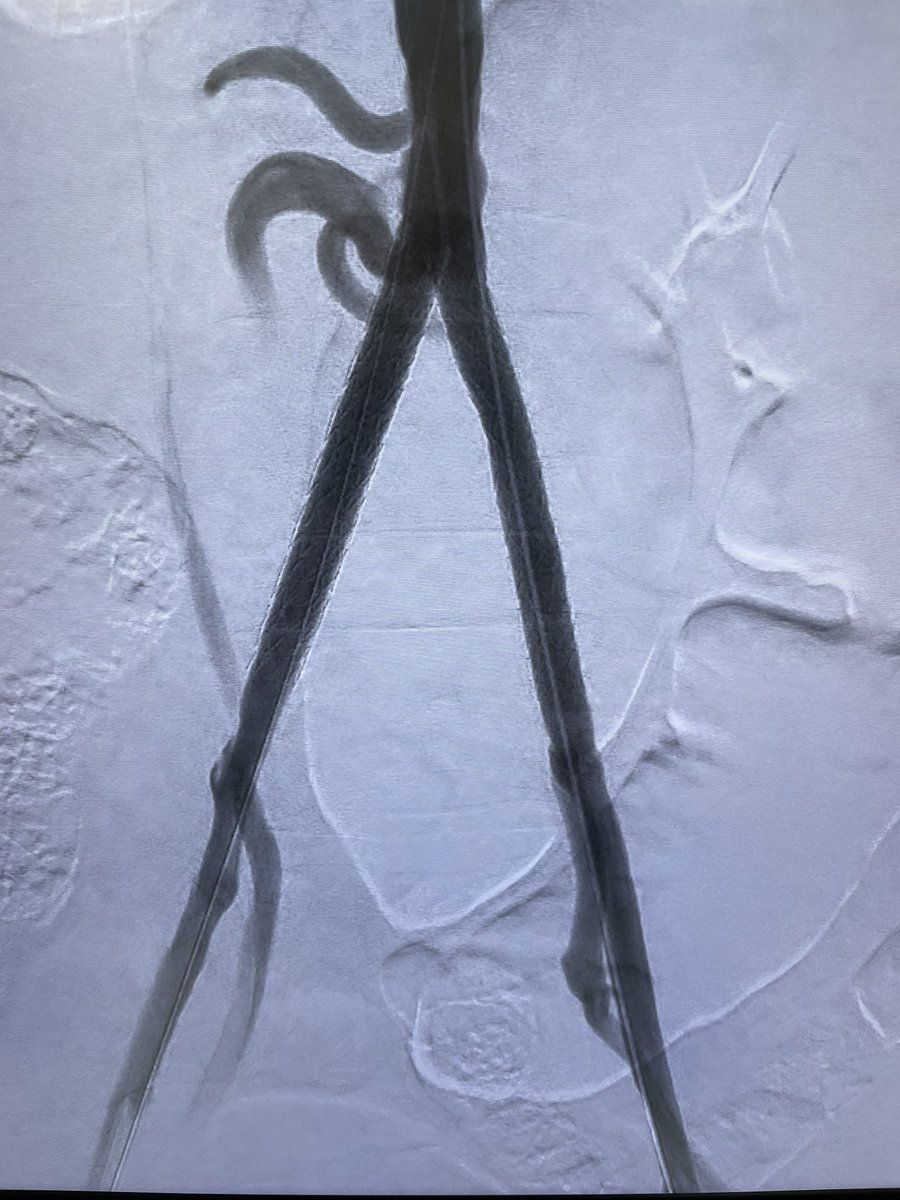

It is eventually here…took us 4 months to get this ready…lymphangiogram and glue embolization for lymphocele @SIRRFS @SIRspecialists @SIR_ECS @GESTSymposium @CVIR_Journal @RSNA @IR_UMMC @EmoryIRad @billmajdalany @JShaikhVIR youtu.be/yhUjBg-R46s